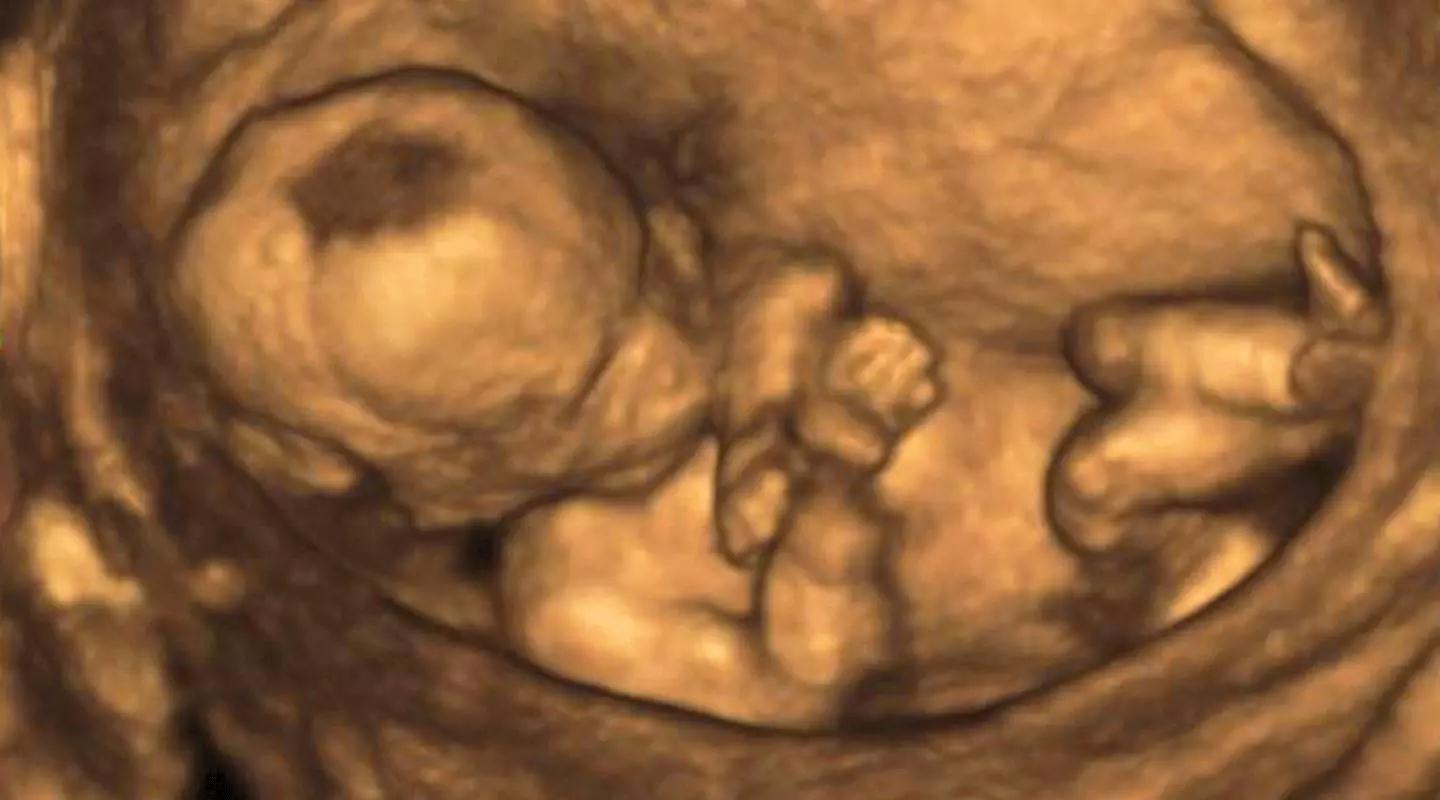

脐带缠绕是指脐带缠绕在胎儿的颈部,躯干,肢体等,大部分缠绕在颈部,所以又称脐带绕颈。

四维彩超(基础版四维彩超)

+心脏彩超